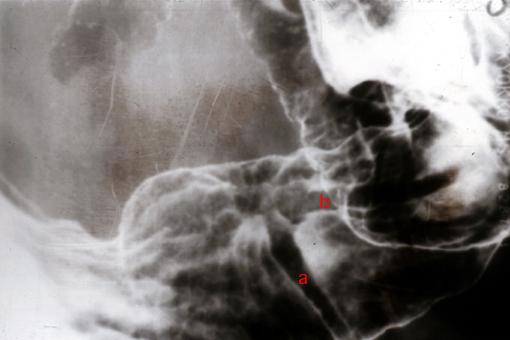

疾病(病理主体)的分类恶性上皮性肿瘤/腺癌

部位(按器官分)胃(部位)/前庭

检查方法X线

肿瘤的肉眼分类0型(表在型)/IIc型(IIc)

肿瘤最大直径15~19

肿瘤的深度sm